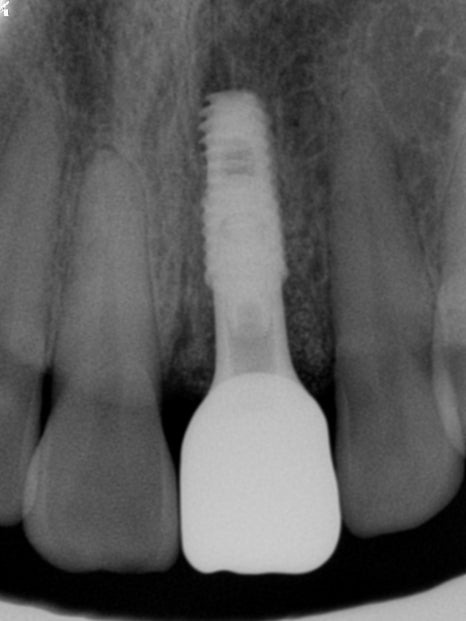

발치와 동시에 임플란트를 식립한 후 방사선사진

임플란트 수술이 잘 이루어지고 난 후에는